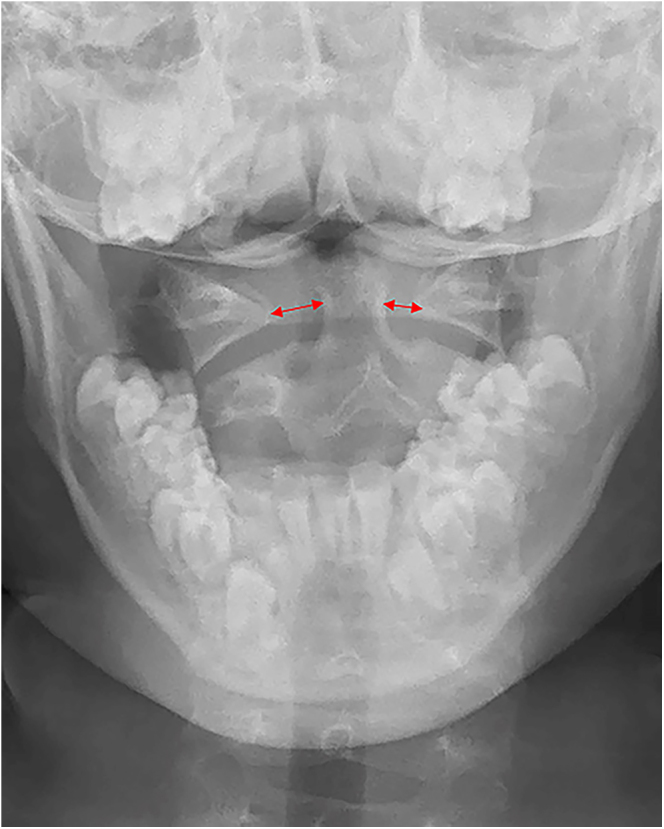

Radiography is of importance in the diagnosis of atlantoaxial dislocation (AAD), and it is the basic imaging technique. However, it should not be the sole diagnostic modality, especially in complex or unclear cases. Conventional X-ray includes an open-mouth odontoid view and a cross-table lateral view, and careful study of radiological findings is crucial to give an early diagnosis of AAD. Lateral flexion-extension dynamic views are only used as an additional supplement in some special cases. Although X-ray images are enough to diagnose AAD in most cases, some patients suspected with AAD should be evaluated with the readily available and quick CT scan. If patients with AAD have symptoms of spinal cord and medullary compression, apart from conventional radiographs, a combination of high-quality CT and MRI of cervical spine are necessary for the diagnosis and choice of treatment. For patients with AAD, both the thin slice CT scanning with coronal, sagittal and three-dimensional reconstruction images and MRI of cervical spine are fundamental to surgical planning. Clinical classifications of AAD associated with imaging are useful in determining treatment strategies. The present study reviews publications on imaging and clinical classification of AAD to aid the clinician in the evaluation and management of these dislocations.